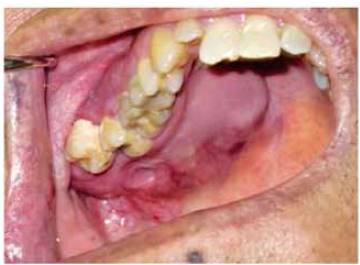

Se presenta un paciente masculino de 68 años de edad, a los servicios de Patología y Medicina Bucal de la Universidad Latina de Costa Rica en el año 2012, mostrando una tumoración unilateral derecha de alrededor de 5 años de evolución la cual, según relata el paciente, había sido diagnosticada originalmente como un hemangioma. Extrabucalmente, la lesión genera una leve asimetría de las regiones bucal, zigomática e infraorbitaria (figura 1). Intrabucalmente se delimita una tumoración en el maxilar que abarca extensamente el paladar duro, la tuberosidad maxilar y parte del hueso alveolar del cuadrante superior derecho.

Figura 1 Fotografía clínica mostrando asimetría facial de las regiones bucal, zigomática e infraorbitaria

Durante la inspección intrabucal, la lesión se encontró firme a la palpación, indolora y en gran parte de la mucosa se observa de color rosa pálido, otras zonas presentan telangiectasia, irritación y leve inflamación (figura 2). Las piezas molares del cuadrante superior derecho, particularmente la tercera molar, han sido desplazadas hacia vestibular por el crecimiento de la lesión. La mucosa retromolar presenta marcada en su superficie la cara oclusal de la tercera molar inferior derecha, debido a que esta ocluye contra la mucosa, tanto por el tamaño de la lesión como por el desplazamiento que ha ejercido sobre las piezas dentales superiores.

Figura 2 Fotografía intrabucal que muestra la extensión de la lesión. Nótese marcada en la mucosa la cara oclusal de la tercera molar inferior derecha.